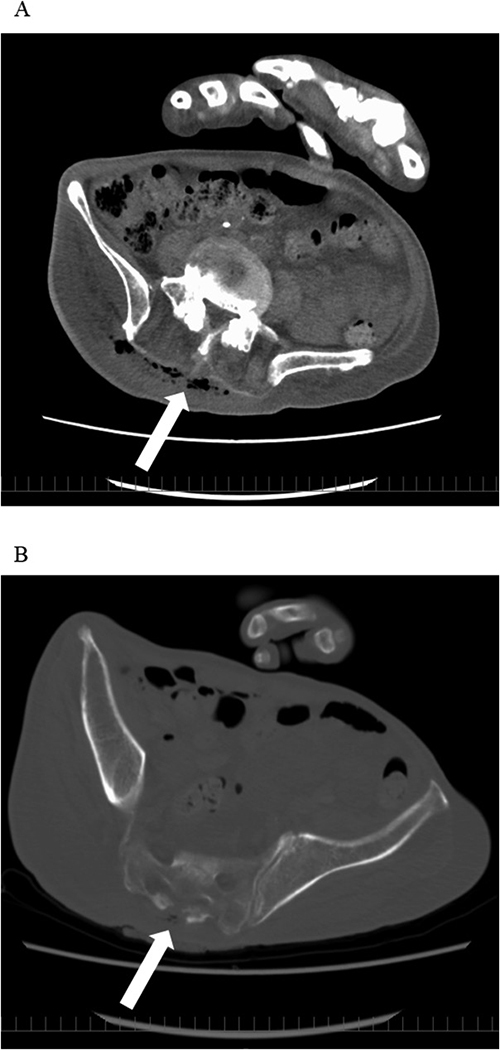

这是首例褥疮感染和副褥疮威洛菌(V. Veillonella parvula)菌血症的病例报告。一名 70 多岁的患者因褥疮感染入院,开始接受他唑巴坦/哌拉西林治疗。在血液和褥疮部位的培养物中检测到了耐他唑巴坦/哌拉西林的伞菌。抗菌治疗改为克林霉素和头孢美唑。抗菌治疗持续了 28 天。患者被转到一家疗养医院。伴有糖尿病等基础疾病的免疫力低下患者偶尔会感染副猪弧菌。通过培养试验进行适当的评估对于诊断、治疗和预防复发非常重要。他唑巴坦/哌拉西林常用于治疗多种细菌感染,如褥疮感染。伞菌可能对他唑巴坦/哌拉西林产生耐药性,因此在治疗时应考虑到这种可能性。

This is the first case report of decubitus infection and bacteremia due to Veillonella parvula (V. parvula). A patient in his 70s with pre-existing diabetes mellitus was admitted with decubitus infection, and tazobactam/piperacillin treatment was initiated. Tazobactam/piperacillin-resistant V. parvula was detected in the blood and decubitus site cultures. The antimicrobial treatment was changed to clindamycin and cefmetazole. Antimicrobial therapy was administered for 28 days. The patient was transferred to a convalescent hospital. V. parvula occasionally causes infection in immunocompromised patients with underlying diseases, such as diabetes. An appropriate evaluation by culture test is important for diagnosis, treatment, and recurrence prevention. Tazobactam/piperacillin is often used in the treatment of multi-bacterial infections such as decubitus infections. V. parvula may be resistant to tazobactam/piperacillin, and this possibility should be taken into account when administering treatment.